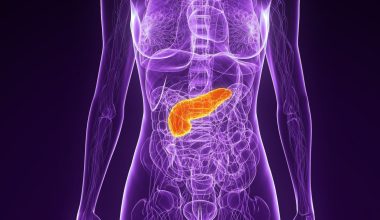

Θα πρέπει να γνωστοποιηθεί πώς η ιδιοπαθής πνευμονική ίνωση (ΙΠΙ), αποτελεί μια σπάνια πάθηση των πνευμόνων η οποία κάνει τον ιστό στους πνεύμονες να γίνει δύσκαμπτος.

Δεν είναι σαφές γιατί αναπτύσσεται εξαρχής η ιδιοπαθής πνευμονική ίνωση. Κάθε περίπτωση ΙΠΙ είναι διαφορετική.

Ιδιοπαθής πνευμονική ίνωση: Πιθανά αίτια

Οι γιατροί μπορεί να εξετάσουν διάφορες πιθανές αιτίες κατά τη διάγνωση της πνευμονικής ίνωσης.

Αυτές μπορεί να είναι:

- περιβαλλοντικοί παράγοντες, όπως έκθεση σε ρύπανση και τοξίνες

- φάρμακα

- ακτινοθεραπεία

- λοιμώξεις

- άλλες ασθένειες

Ωστόσο, στην πλειονότητα των περιπτώσεων πνευμονικής ίνωσης, οι γιατροί δεν είναι σε θέση να προσδιορίσουν την αιτία. Εάν δεν μπορούν να βρουν την αιτία, η ασθένεια θα χαρακτηριστεί ως ιδιοπαθής.

Οι γενετικοί παράγοντες μπορεί να παίζουν κάποιο ρόλο στην ανάπτυξη της ΙΠΙ, αλλά είναι σπάνιο να εμφανιστεί σε περισσότερα από ένα μέλη της ίδιας οικογένειας.

Ιδιοπαθής πνευμονική ίνωση: Συμπτώματα

Η ιδιοπαθής πνευμονική ίνωση προκαλεί ουλές και ακαμψία στους πνεύμονες. Με την πάροδο του χρόνου, οι ουλές θα γίνουν σοβαρές και η ακαμψία θα δυσκολέψει την αναπνοή.

Τα κοινά συμπτώματα είναι:

- δυσκολία στην αναπνοή

- χρόνιος βήχας

- δυσφορία στο στήθος

- αδυναμία

- κούραση

- απώλεια βάρους

Εν τέλει, οι πνεύμονες μπορεί να μην είναι σε θέση να λάβουν αρκετό οξυγόνο για να τροφοδοτήσουν το σώμα με την ποσότητα που χρειάζεται. Αυτό μπορεί τελικά να οδηγήσει σε αναπνευστική ανεπάρκεια, καρδιακή ανεπάρκεια και άλλα προβλήματα υγείας.

Υπάρχουν διαφορετικά στάδια ιδιοπαθούς πνευμονικής ίνωσης;

Η ιδιοπαθής πνευμονική ίνωση δεν έχει επίσημα στάδια, αλλά υπάρχουν διακριτές περίοδοι στην εξέλιξη της νόσου.

Όταν διαγνωστείτε αρχικά μπορεί να μην χρειάζεστε βοήθεια οξυγόνου.

Αργότερα, μπορεί να ανακαλύψετε ότι χρειάζεστε οξυγόνο κατά τη διάρκεια καθημερινών δραστηριοτήτων, όπως το περπάτημα και το καθάρισμα.

Όσο οι ουλές στους πνεύμονες γίνονται σοβαρές, πιθανότατα θα χρειάζεστε οξυγόνο ανά πάσα στιγμή, όχι μόνο όταν είστε δραστήριοι, αλλά ακόμη και στον ύπνο.

Η ιδιοπαθής πνευμονική ίνωση προχωρά σταδιακά. Μερικοί ασθενείς θα εμφανίσουν περιοδικές εξάρσεις της νόσου, οπότε η αναπνοή τους θα είναι πιο δύσκολη. Η πνευμονική βλάβη που λαμβάνει χώρα κατά τη διάρκεια αυτών των εξάρσεων δεν είναι αναστρέψιμη και είναι απίθανο να ανακτήσετε κάποια από τις πνευμονικές λειτουργίες, που είχατε πριν από αυτήν.

Πώς αντιμετωπίζεται η ιδιοπαθής πνευμονική ίνωση

Υπάρχουν διαθέσιμες επιλογές θεραπείας, για να σας βοηθήσουν να διαχειριστείτε και να μειώσετε τα συμπτώματά σας.

Οι κύριοι στόχοι της ιατρικής θεραπείας είναι η μείωση της φλεγμονής των πνευμόνων, η προστασία του πνευμονικού ιστού και η επιβράδυνση της απώλειας της πνευμονικής λειτουργίας. Αυτό θα σας επιτρέψει να αναπνέετε ευκολότερα.

Οι πιο συνηθισμένες θεραπευτικές επιλογές περιλαμβάνουν οξυγονοθεραπεία και φαρμακευτική αγωγή. οξυγονοθεραπεία βοηθά στην αναπνοή και τα φάρμακα βοηθούν στον έλεγχο της φλεγμονής και στην μείωση των ουλών του πνευμονικού ιστού.

Μπορεί επίσης να απαιτηθεί μεταμόσχευση πνεύμονα. Επειδή είναι μια σημαντική επέμβαση, μια μεταμόσχευση πνεύμονα θεωρείται συχνά ως το ύστατο μέσο θεραπείας. Θεωρείται, ωστόσο, ως η μοναδική πραγματική θεραπεία για την ΙΠΙ.

Ποιες αλλαγές στον τρόπο ζωής μπορούν να βοηθήσουν στη διαχείριση της ιδιοπαθούς πνευμονικής ίνωσης;

Είναι σημαντικό να μάθετε να υιοθετείτε πρακτικές υγιεινού τρόπου ζωής, που μπορούν να μειώσουν τα συμπτώματα και να βελτιώσουν την πρόγνωση και την ποιότητα ζωής σας.

Τέτοιες αλλαγές στον τρόπο ζωής μπορεί να είναι:

- διακοπή του καπνίσματος

- διατήρηση ενός τουλάχιστον μέτριου σωματικού βάρους, το οποίο μπορεί να απαιτεί απώλεια βάρους

- σωστός εμβολιασμός, λήψη φαρμάκων, βιταμινών και συμπληρωμάτων

- διαρκής παρακολούθηση του κορεσμού οξυγόνου (επίπεδα οξυγόνου στο αίμα), ώστε να είναι πάντα στο βέλτιστο εύρος

Μπορείτε, επίσης, να μάθετε ασκήσεις και τεχνικές για καλύτερη αναπνοή και διαχείριση του στρες και των πολλών συναισθημάτων, που μπορεί να προκαλέσει η διάγνωση μιας σοβαρής νόσου.

Τα εργαλεία εκμάθησης για τη διαχείριση του στρες μπορεί να βοηθήσουν στην πρόληψη της επιδείνωσης των συμπτωμάτων. Ομάδες υποστήριξης μπορούν επίσης να μειώσουν το άγχος και τα συναισθήματα μοναξιάς, καθώς έχετε απορίες ή αβεβαιότητα για την εξέλιξη της νόσου.

Ιδιοπαθής πνευμονική ίνωση: Πρόγνωση και πιθανές επιπλοκές

Η ιδιοπαθής πνευμονική ίνωση είναι μια προοδευτική ασθένεια, που σημαίνει ότι θα επιδεινωθεί με την πάροδο του χρόνου. Αν και μπορείτε να λάβετε μέτρα για να διαχειριστείτε τα συμπτώματα, δεν μπορείτε να σταματήσετε εντελώς τις ουλές και τη βλάβη στους πνεύμονες.

Για μερικούς ασθενείς, η νόσος μπορεί να εξελιχθεί πολύ γρήγορα. Για άλλους, μπορεί να χρειαστούν πολλά χρόνια προτού τα αναπνευστικά προβλήματα είναι τόσο δύσκολα, ώστε να χρειάζεστε συνεχώς επιπλέον οξυγόνο.

Όταν η πνευμονική λειτουργία περιορίζεται σοβαρά, μπορεί να προκαλέσει σοβαρές επιπλοκές, όπως:

- καρδιακή ανεπάρκεια

- αναπνευστική ανεπάρκεια

- πνευμονία

- πνευμονική υπέρταση

- πνευμονική εμβολή (θρόμβος αίματος στους πνεύμονες)

Τα υπάρχοντα συμπτώματα μπορεί επίσης να επιδεινωθούν ξαφνικά μετά από λοίμωξη, καρδιακή ανεπάρκεια, ή πνευμονική εμβολή.

Η χειρουργική επέμβαση μεταμόσχευσης μπορεί να βοηθήσει στη βελτίωση της προοπτικής σας. Άλλες θεραπείες και αλλαγές στον τρόπο ζωής μπορούν επίσης να βοηθήσουν στην επιβράδυνση της εξέλιξης της νόσου.